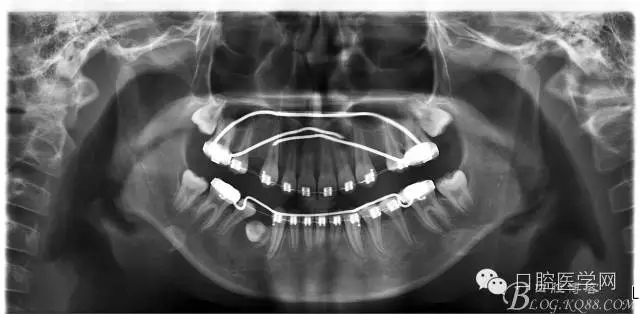

查:右側(cè)第二前磨牙第一乳磨牙恒尖牙頰側(cè)前庭溝隆起,捫有乒乓球感。曲斷及CT示:右側(cè)第二前磨牙第一乳磨牙恒尖牙根尖區(qū)有一囊腫,頰舌側(cè)骨板極薄,牙根無(wú)吸收,第二前磨牙牙根位于囊腫中,第一雙尖牙牙冠遠(yuǎn)中水平向阻生,牙冠位于囊腫中。經(jīng)協(xié)議:手術(shù)摘除創(chuàng)傷大,同意開(kāi)創(chuàng)引流保守治療。

否認(rèn)手術(shù)禁忌癥及過(guò)敏史。消毒,局麻下鋪巾,拔出第一乳磨牙,有囊液溢出,擴(kuò)大開(kāi)放引流孔,取部分囊壁送病理,生理鹽水沖洗,置引流管縫合固定。病理報(bào)告:囊腫。八月后局麻拔除第一雙尖牙刮凈剩余變小的囊壁。

術(shù)后一個(gè)月 三個(gè)月 五個(gè)月 八個(gè)月 拔除第一雙尖牙后 曲斷片: